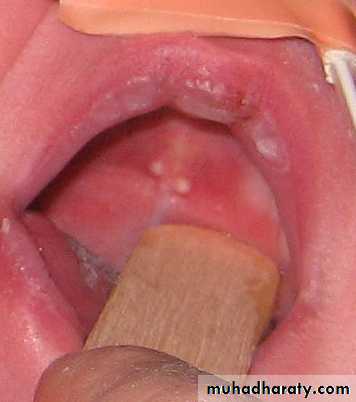

Pharangitis

2 chronic non suppurative complication>> psgn , rhumatic fever2 ddx >> im , diphtheria

Acute tonsillitis

Complication otitis mmedia , quinsy , retropharyngeal abscessCellulitis